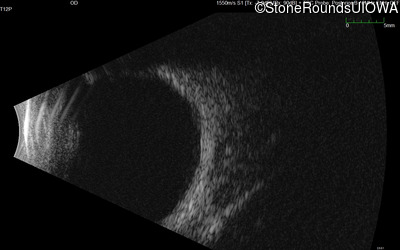

B-Scan Ultrasonography - Right - 20/600

Exemplar